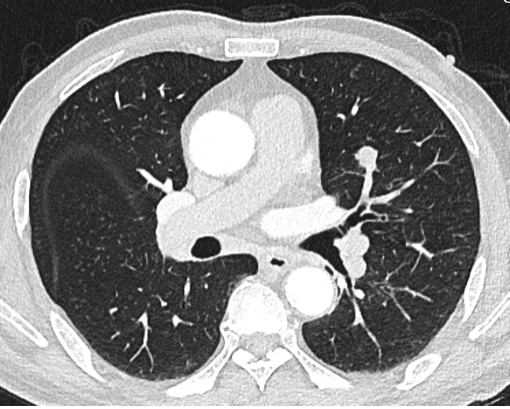

image.png

图二:实性结节